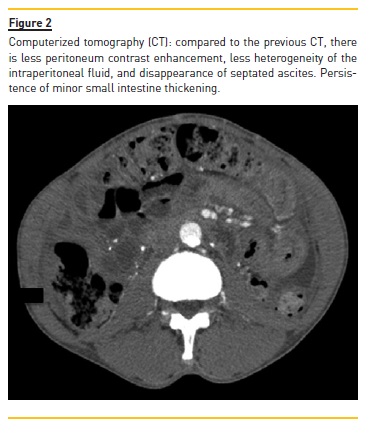

Ultrasonography showed septated echogenic non‑pure ascites. Computerized tomography showed septated ascites, visceral peritoneal thickening of the intestinal loops with contrast enhancement, and minor small intestine wall thickening without major intestinal distension (Figure 1). Peritoneal fluid obtained by paracentesis presented a bloody appearance. A peritoneal total and differential fluid cell count showed increased leukocytes (880 /uL) with predominant mononuclear cells (51.6%; 675 /μL) and raised erythrocytes (58000 /uL), and the chemical analysis was compatible with an exudate (proteins 5.4 g/dL, LDH 289 U/L, amylase 66 U/L, glucose 58 mg/dL).

In summary, a previously stable male HD patient presented to the hospital with fever, anorexia, increased abdominal volume, worsening anemia, increased inflammatory markers, septated ascites, and visceral peritoneal thickening of the intestinal loops. The embedded PD catheter was exteriorized and hemoperitoneum was confirmed. Thus, a diagnosis of EPS was considered. Treatment was initiated with daily peritoneal lavage, oral nutritional support, oral prednisolone 0.5 mg/kg/day (6 days), and tamoxifen 20 mg every 12 h. The patient presented complete resolution of the symptoms and regularization of inflammatory markers over the following days. A second CT showed less peritoneal contrast enhancement, less heterogeneity of the intraperitoneal fluid, disappearance of septated ascites, and persistence of minor small intestine thickening (Figure 2).). Despite losing weight during admission, the patient recovered appetite and was discharged on oral prednisolone and tamoxifen, with 58.2 kg. The patient received nutritional counseling from a dietician at the hemodialysis clinic, initiated a hypercaloric diet and his condition was regularly evaluated.